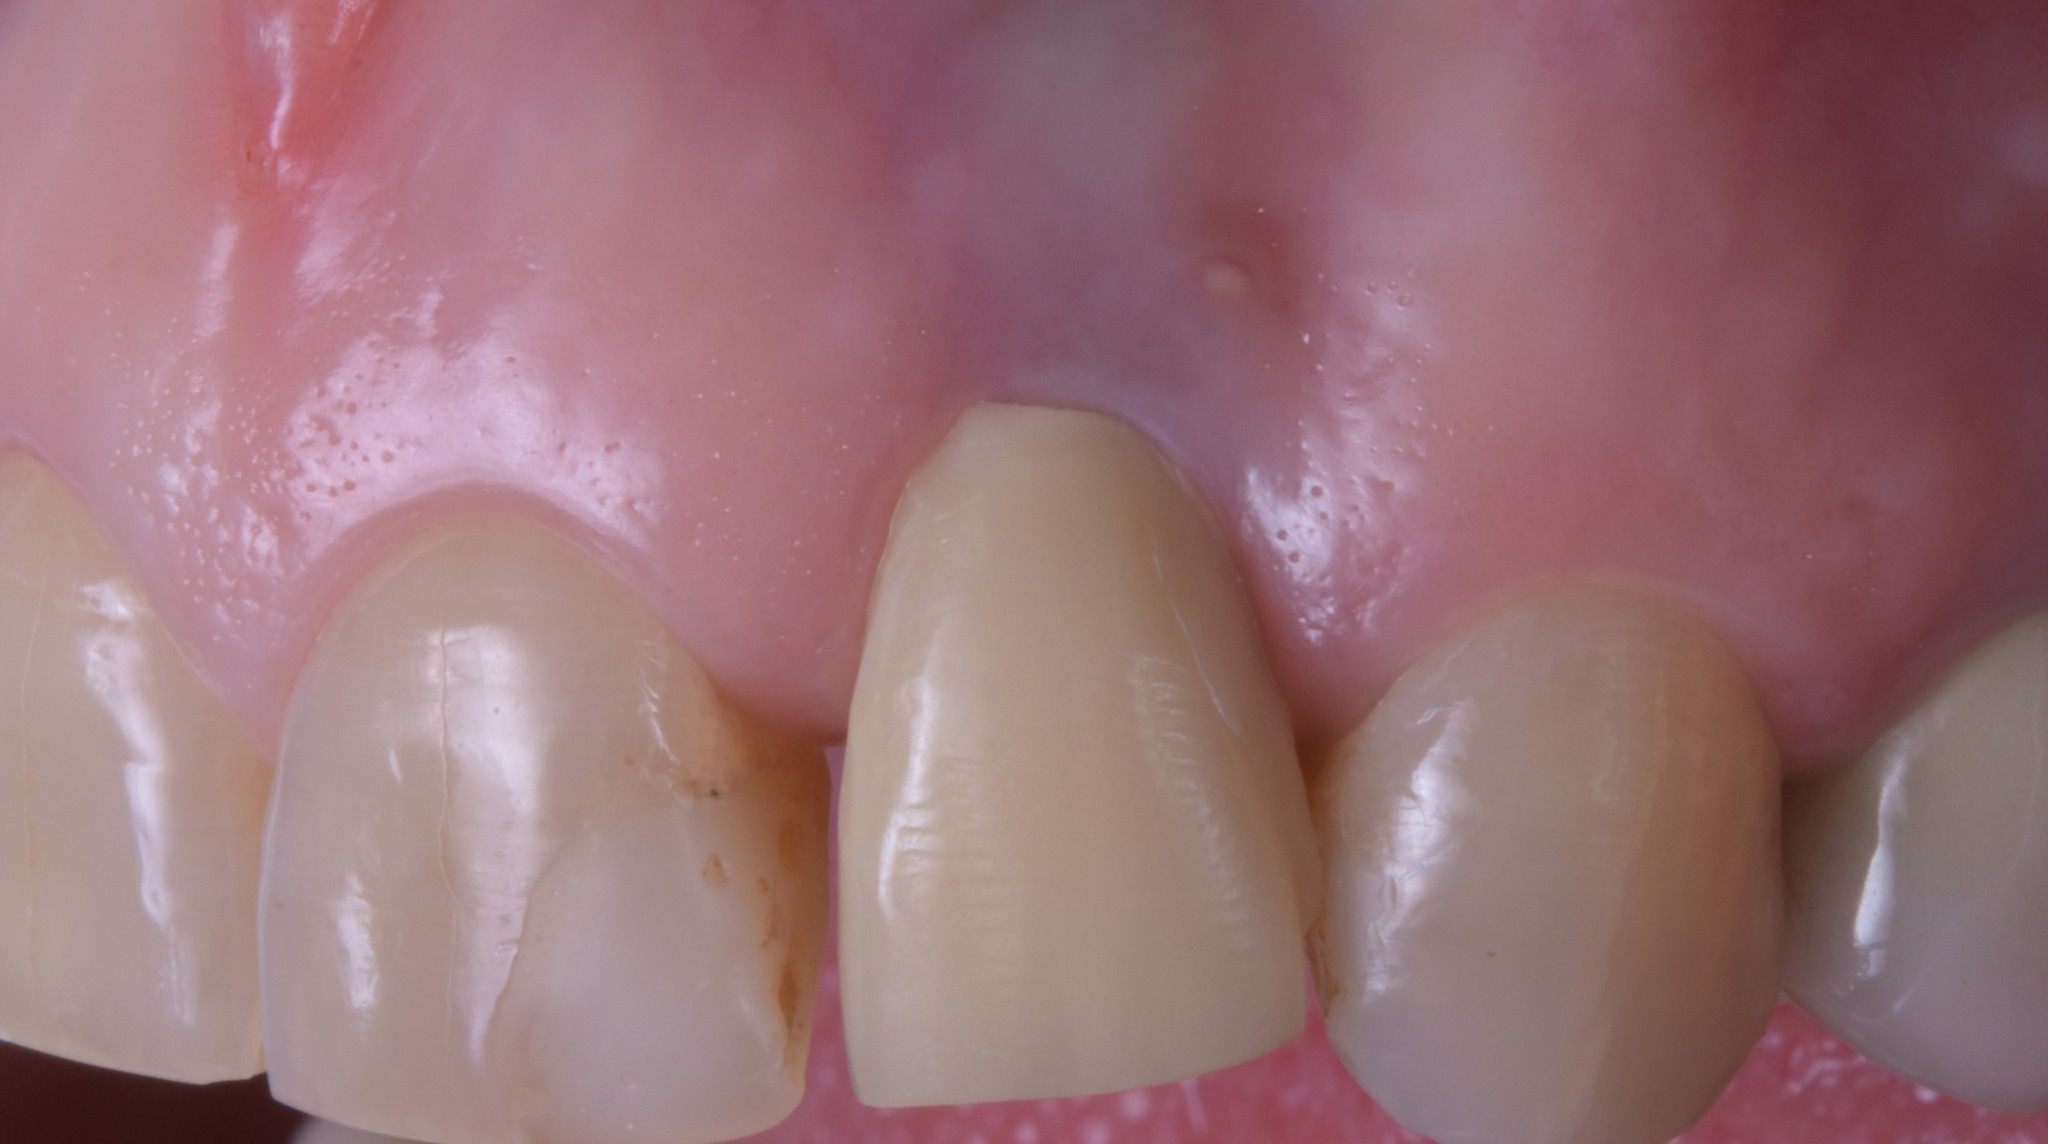

corso gestione tessuti molli - guarigione 1

corso gestione dei tessuti molli - guarigione 2

Ti mostro la foto a sette giorni per due motivi.

• La bellezza di una chirurgia si valuta dalla guarigione a sette giorni. Se aspetti 2 anni, alla fine anche una chirurgia di merda guarisce.

• Ho operato la paziente 7 giorni fa e non ho foto più recenti ma penso che concorderai con me che dopo una guarigione così difficilmente avremo delle sorprese.

Come puoi vedere abbiamo risolto completamente il deficit dei tessuti molli che era stato lasciato dopo le precedenti terapie e…

… posto le basi per una nuova riabilitazione definitiva che si possa definire esteticamente degna dei tempi in cui abbiamo la fortuna di vivere.